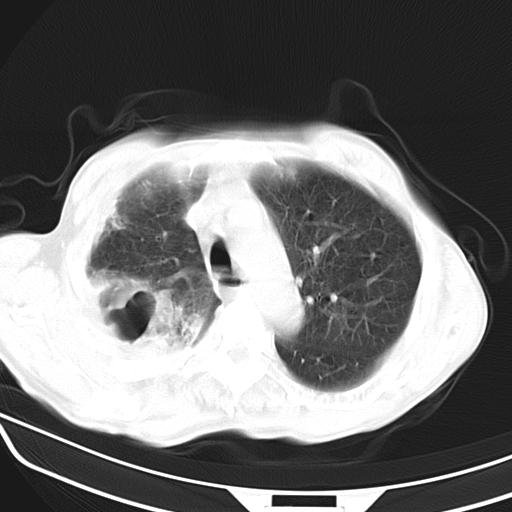

抗炎治疗10天后复查

抗炎治疗10天后复查:右上肺模糊阴影明显减少。